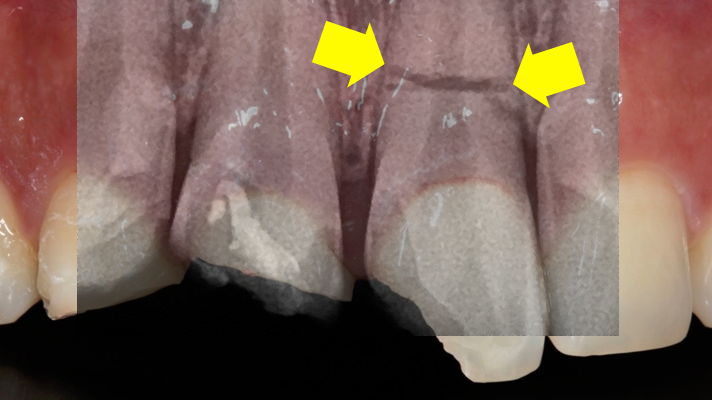

Clinical case: Extraction, immediate placement & loading using

R2GATE solution in aesthetic zone

- Courtesy of Dr. Jong-Cheol Kim, Korea-

Dr. Jong Cheol Kim, immediate loading, digital guided surgery, Digital ONE-DAY Implant, maxillary anterior, #21, guided surgery, immediate loading, AnyRidge, R2GATE, Mega ISQ, MEG Torq, R2GATE Full Surgical Kit

AnyRidge implant system, R2 Guide, R2GATE Full Surgical Kit, Mega ISQ